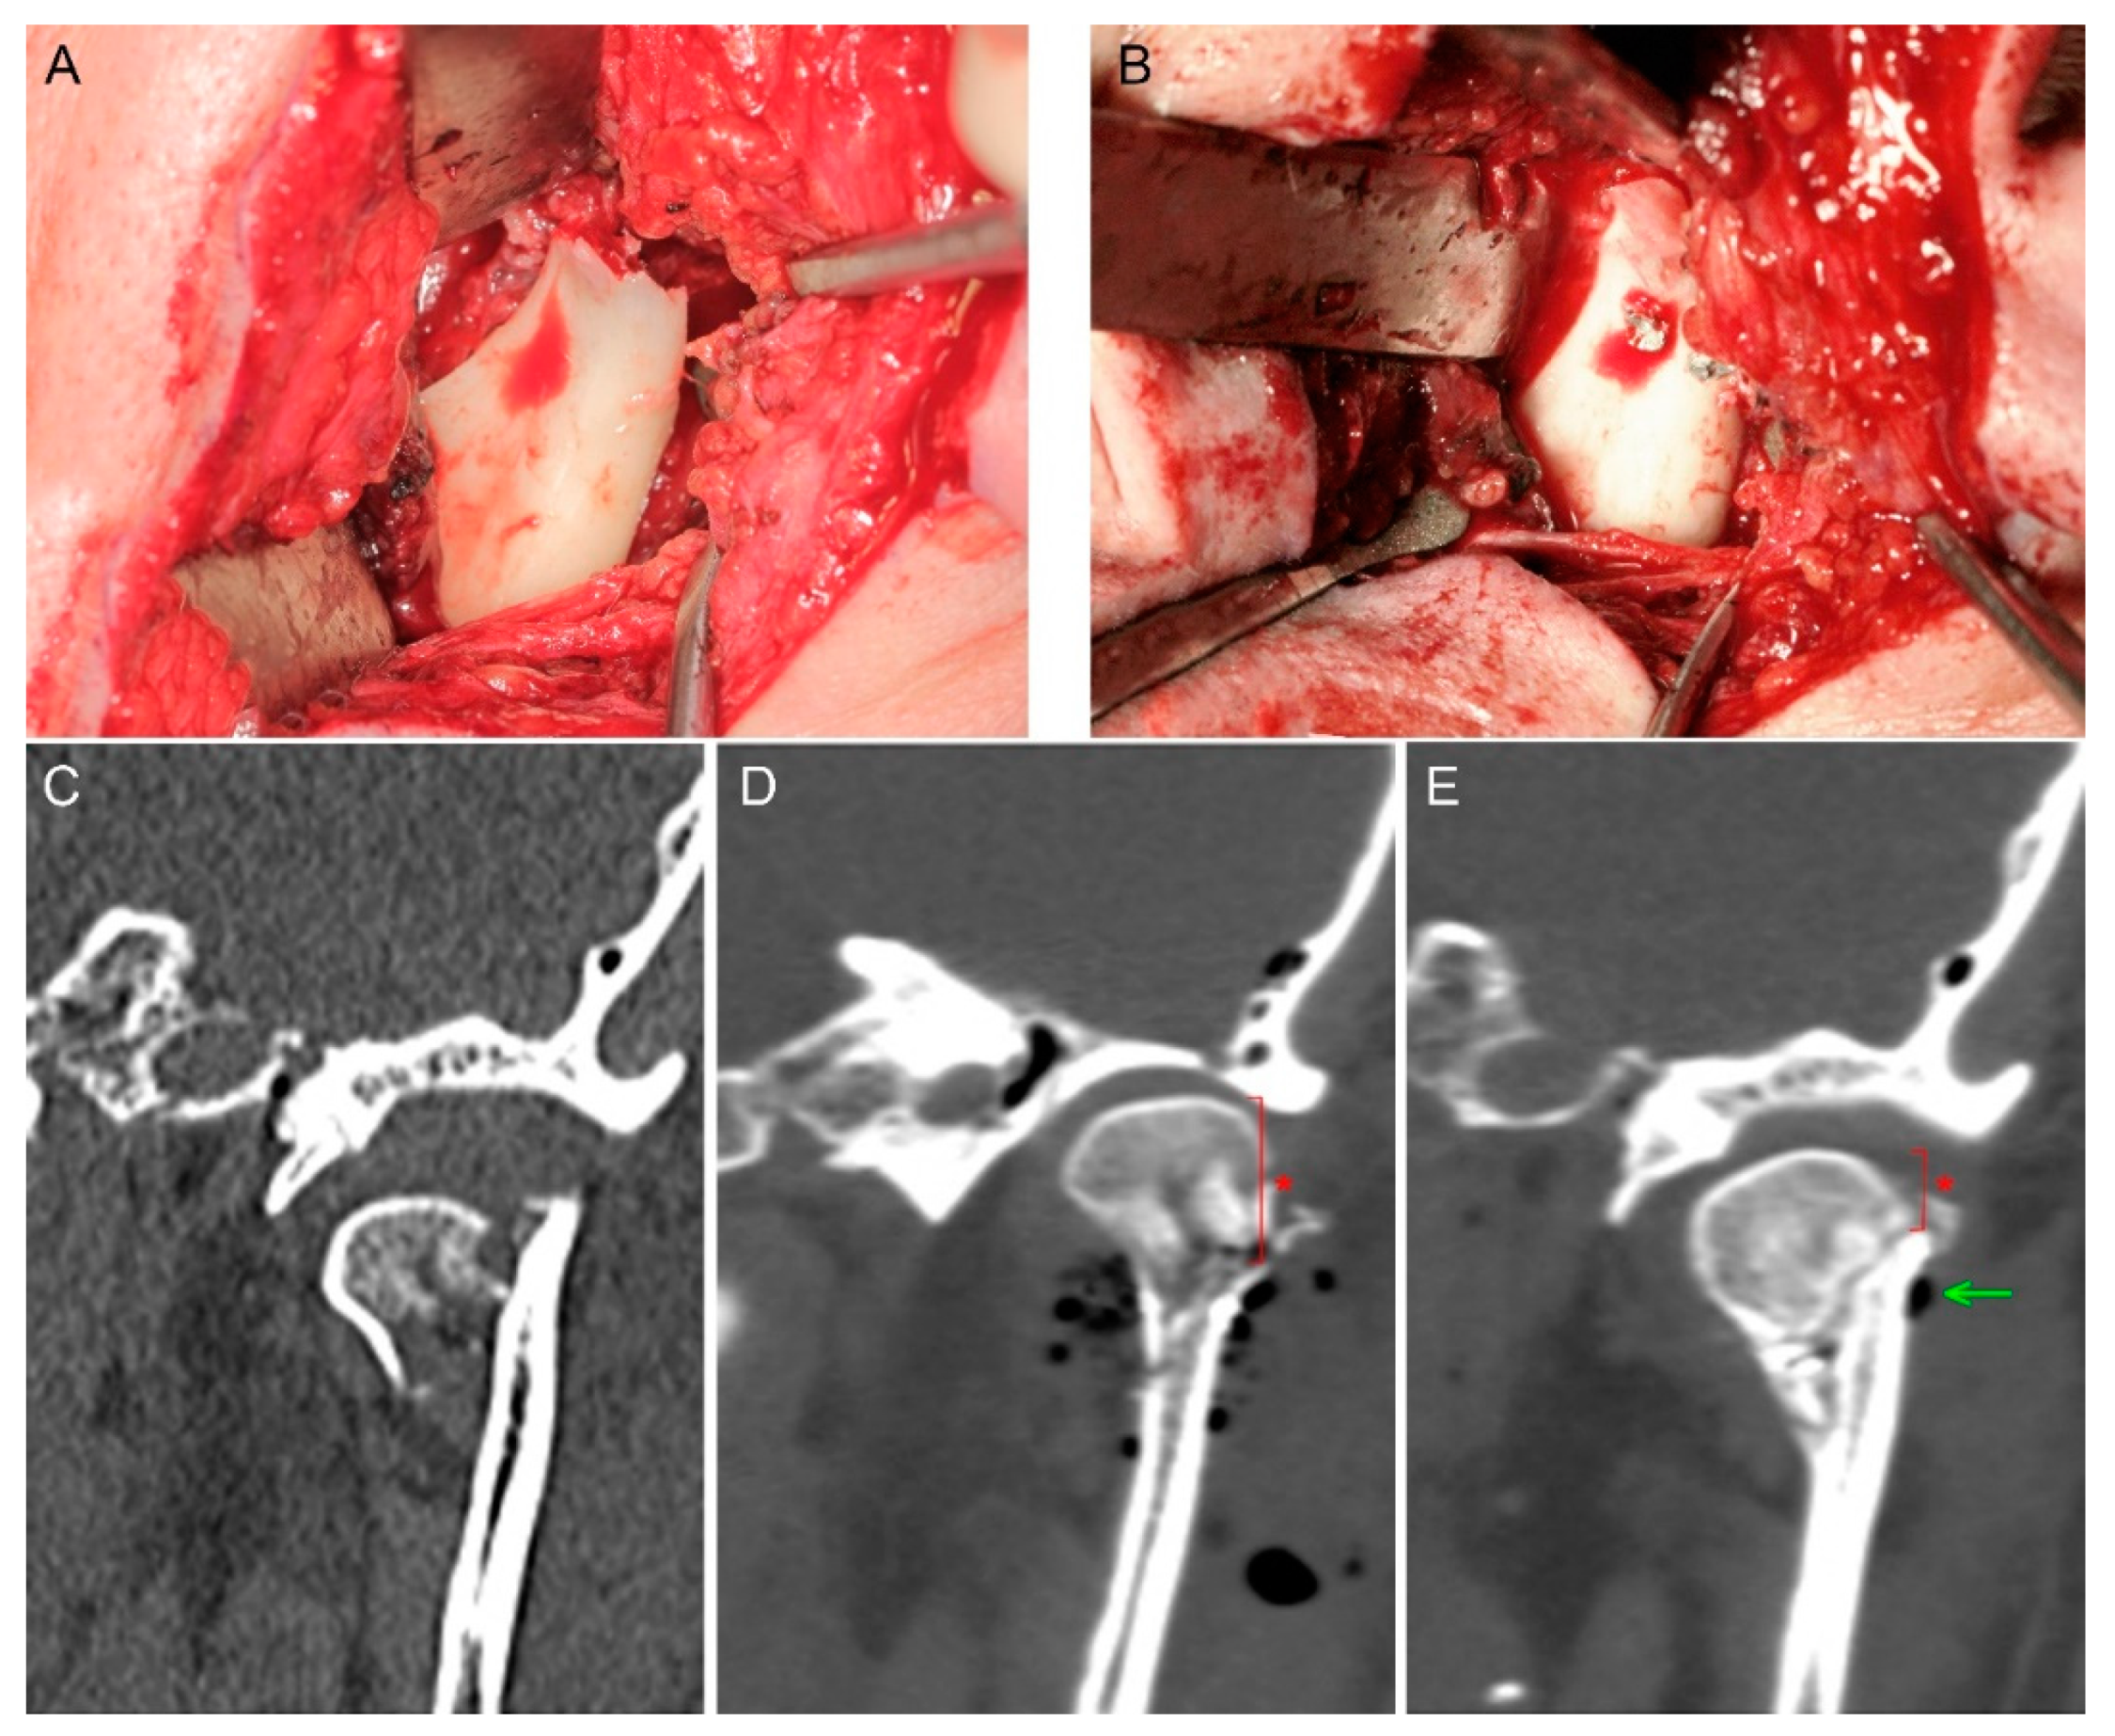

Nowadays, the magnesium alloys used have twice as low Young’s modulus (E = 45,000 MPa) as commonly used titanium grade 5 and 23 (96,000 MPa); approximation of this previous value to the condition of compact bone may be considered a biological advantage of magnesium fixation. Despite this lower E value, the modulus of elasticity in the tension of magnesium alloy is still much higher than that of clinically used resorbable polymers (3000–10,000 MPa) [23]. These conditions have an obvious influence on the lower stability of PLGA fixation, and it is worth considering that they may affect the stability of the screw pulling out of its original position caused by screw absorption (Figure 3).

Figure 3. Mandibular head fracture fixation. The phenomenon of reduced mandibular ramus height appeared (asterisk). (A) Fracture site. (B) Osteosynthesis by two magnesium 1.7 mm × 14 mm screws. (C) Pre-op scan—the mandibular head is dislocated downward which shortens the mandibular ramus. (D) Fixation by compressive headless screws; visible gas bubbles are the air introduced into the wound during open reduction; height of mandible head is marked by an asterisk. (E) 6-month post-op follow-up—fixed bone remodeling, remnants of the produced hydrogen gas (arrow), shortening of the mandibular ramus as a result of the proximal fragment (mandible head) down-shifting along the fissure of the fracture (asterisk).

To date, there is no ideal material for osteosynthesis. On the one hand, in the case of polymers, edema persisting for several months around the foreign body is described [25,60]. On the other hand, in the case of magnesium alloys, hydrogen production around the fixation for a few months is known (Figure 3E). It now seems that the use of resorbable metal alloys with a higher stiffness than resorbable polymers for mandibular head fixation [61] is a good option for traumatology patients provided that surgeons know the mechanical properties of the material, which influences changes in the forces holding the screws in place during bone healing together with metal resorption (Table 1).